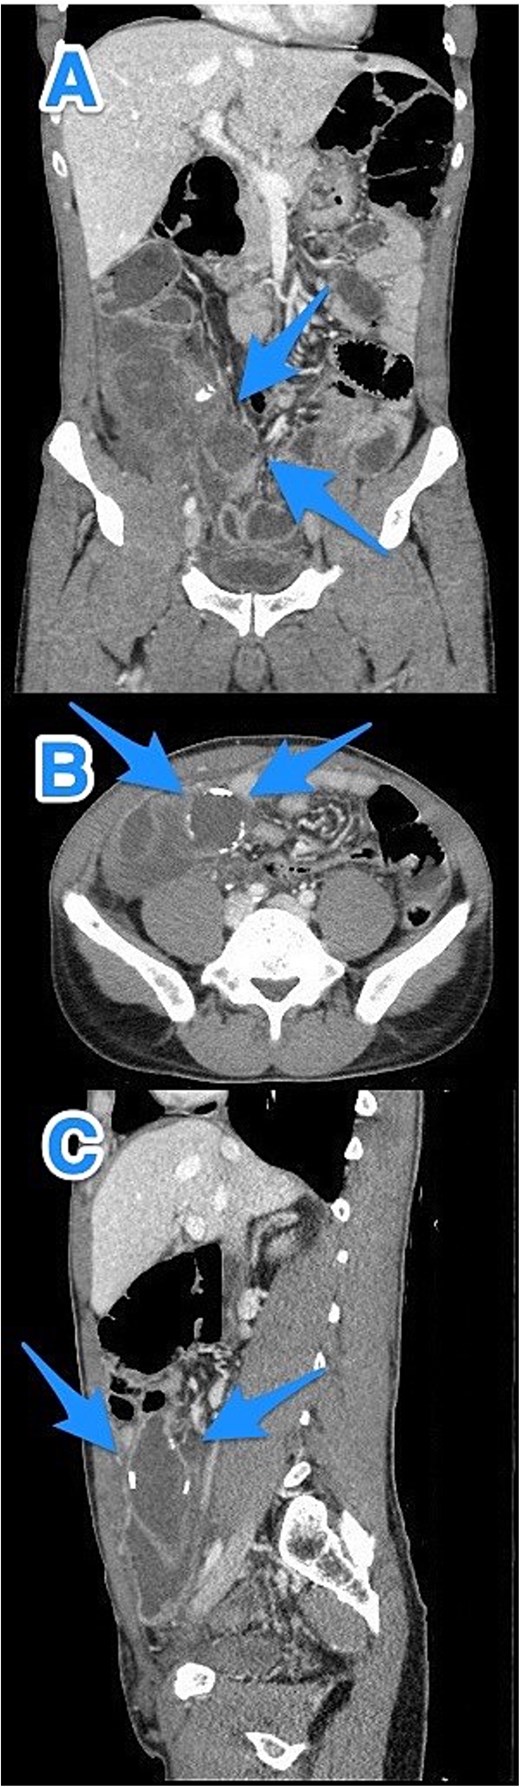

A 47-year-old male patient, with a documented history of diabetes mellitus but no previous surgical interventions, presented with right lower quadrant (RLQ) abdominal pain, which was associated with recurrent vomiting episodes (four times) within the preceding 24 h. The pain did not radiate and was not aggravated by any specific factors. The patient denied fever, urinary symptoms, and changes in bowel habits. On physical examination, he appeared well, with mild pain but no distress. Abdominal examination revealed minimal tenderness and rebound tenderness in the RLQ, but the abdomen was otherwise soft and lax, with no evidence of guarding, rigidity, or fullness. The patient’s laboratory profile was within normal ranges. Abdominal computed tomography (CT) with contrast revealed a dilated, fluid-filled appendix with a maximum diameter of 2.2 cm and tiny peripheral calcifications. There was no surrounding fat stranding or free fluid. The rest of the bowel loops were grossly unremarkable (Fig. 1). A diagnosis of appendicular mucocele was made, and the patient underwent an open appendectomy. The patient’s postoperative course remained clinically uneventful. Gross findings of the appendectomy specimen measured 6 × 2.5 × 2 cm, with a smooth outer surface and no identified perforation. Pathology examination revealed LAMN, confined to the appendix. The sections showed flat mucinous epithelium originating from the lumen, and there was no evidence of extra-appendiceal mucinous extension. The margin was negative for mucinous neoplasm (Fig. 2). A referral to the Colorectal Surgery Clinic was arranged to ensure a thorough evaluation and appropriate follow-up.

CT abdomen and pelvis with contrast—Axial (A) and sagittal (B) views highlighting a dilated, fluid-filled appendix with a maximum diameter of 2.2 cm and small peripheral calcifications (arrows).